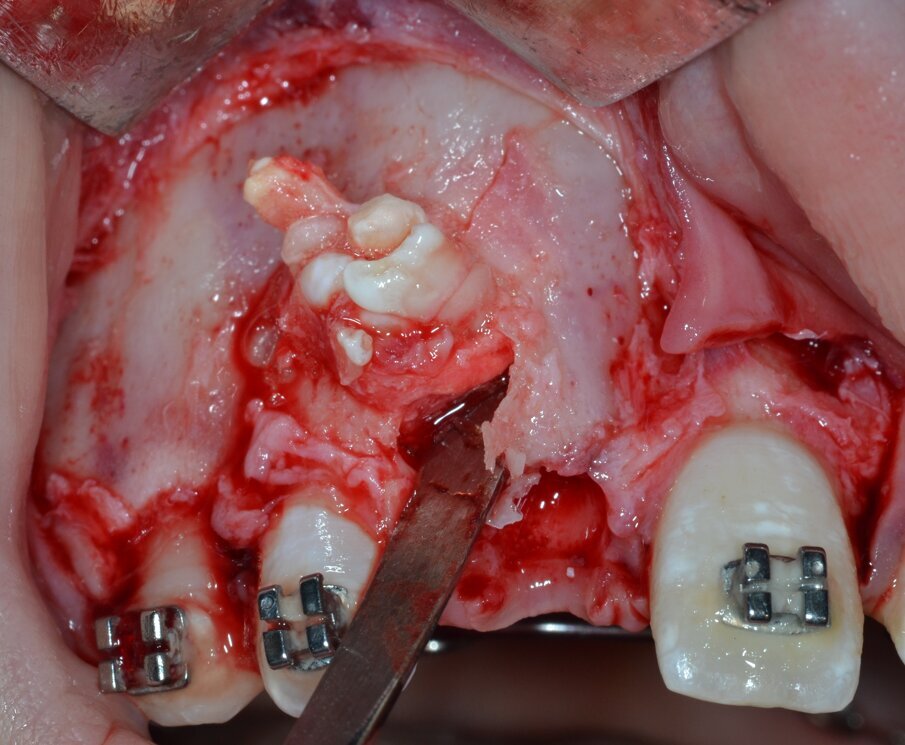

Si procede al clivaggio e all’enucleazione in toto della massa neoformata mediante una leva dritta (Fig. 9) seguita da un’accurata revisione chirurgica della cripta ossea residua (Fig. 10). Il pezzo operatorio viene inviato per l’esame istologico, che confermerà in via definitiva la diagnosi di odontoma composto (Figg. 11, 12). Poiché il piano di trattamento prevede di eseguire l’ancoraggio ortodontico dell’elemento ritenuto nella stessa seduta operatoria, la corona dentaria dell’elemento 1.1 viene esposta chirurgicamente per mezzo di un inserto piezoelettrico dedicato montato su un manipolo ad ultrasuoni (ES010T Esacrom Srl, Imola, Italia) (Fig. 13).

Fig. 9_Enucleazione della massa neoformata mediante una leva dritta.

Fig. 11_Misurazione ex vivo del pezzo operatorio.

Fig. 12_Confezionamento e invio del pezzo operatorio per esame istologico.